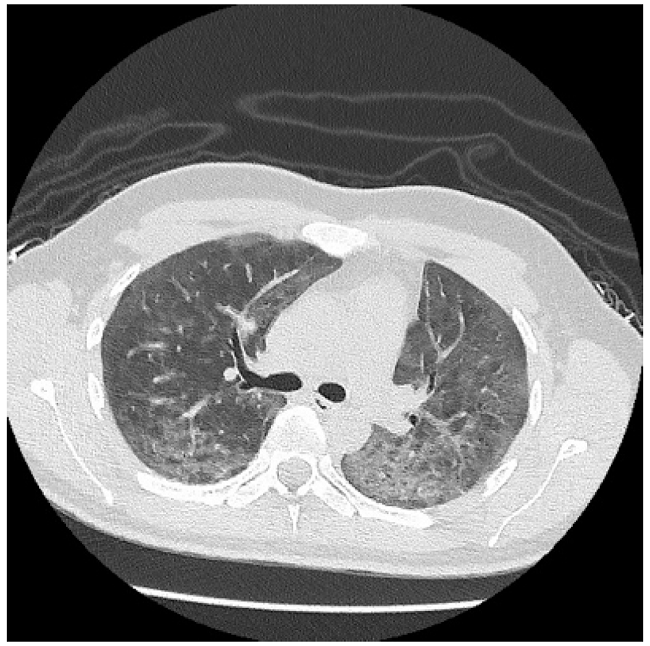

A las 48 horas de hospitalización se confirma diagnóstico de VIH, siendo derivado al hospital de referencia para continuar estudio y tratamiento. En dicho centro se realiza tomografía axial computarizada que confirma patrón de neumonía tipo Pneumocistis jirovecci, tal como se evidencia en las Figuras 2 y 3. Por normativa local, el inicio de la triterapia se indica en el hospital de referencia.